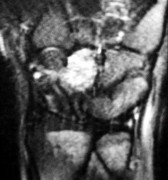

، أو لتقييم مدى تدهور العظم في حالات مثل مرض كينبوك. - التصوير بالرنين المغناطيسي (MRI): ممتاز لتقييم الأنسجة الرخوة مثل الأربطة، الأوتار، الأعصاب، والعضلات. يكشف عن التمزقات،

- الأشعة السينية (X-rays): هي الخطوة الأولى في تقييم الكسور، الخلوع، وتغيرات التهاب المفاصل. تساعد في تحديد مدى تدهور العظام والمسافات المفصلية. على سبيل المثال، تُظهر صور الأشعة السينية كسور السلاميات